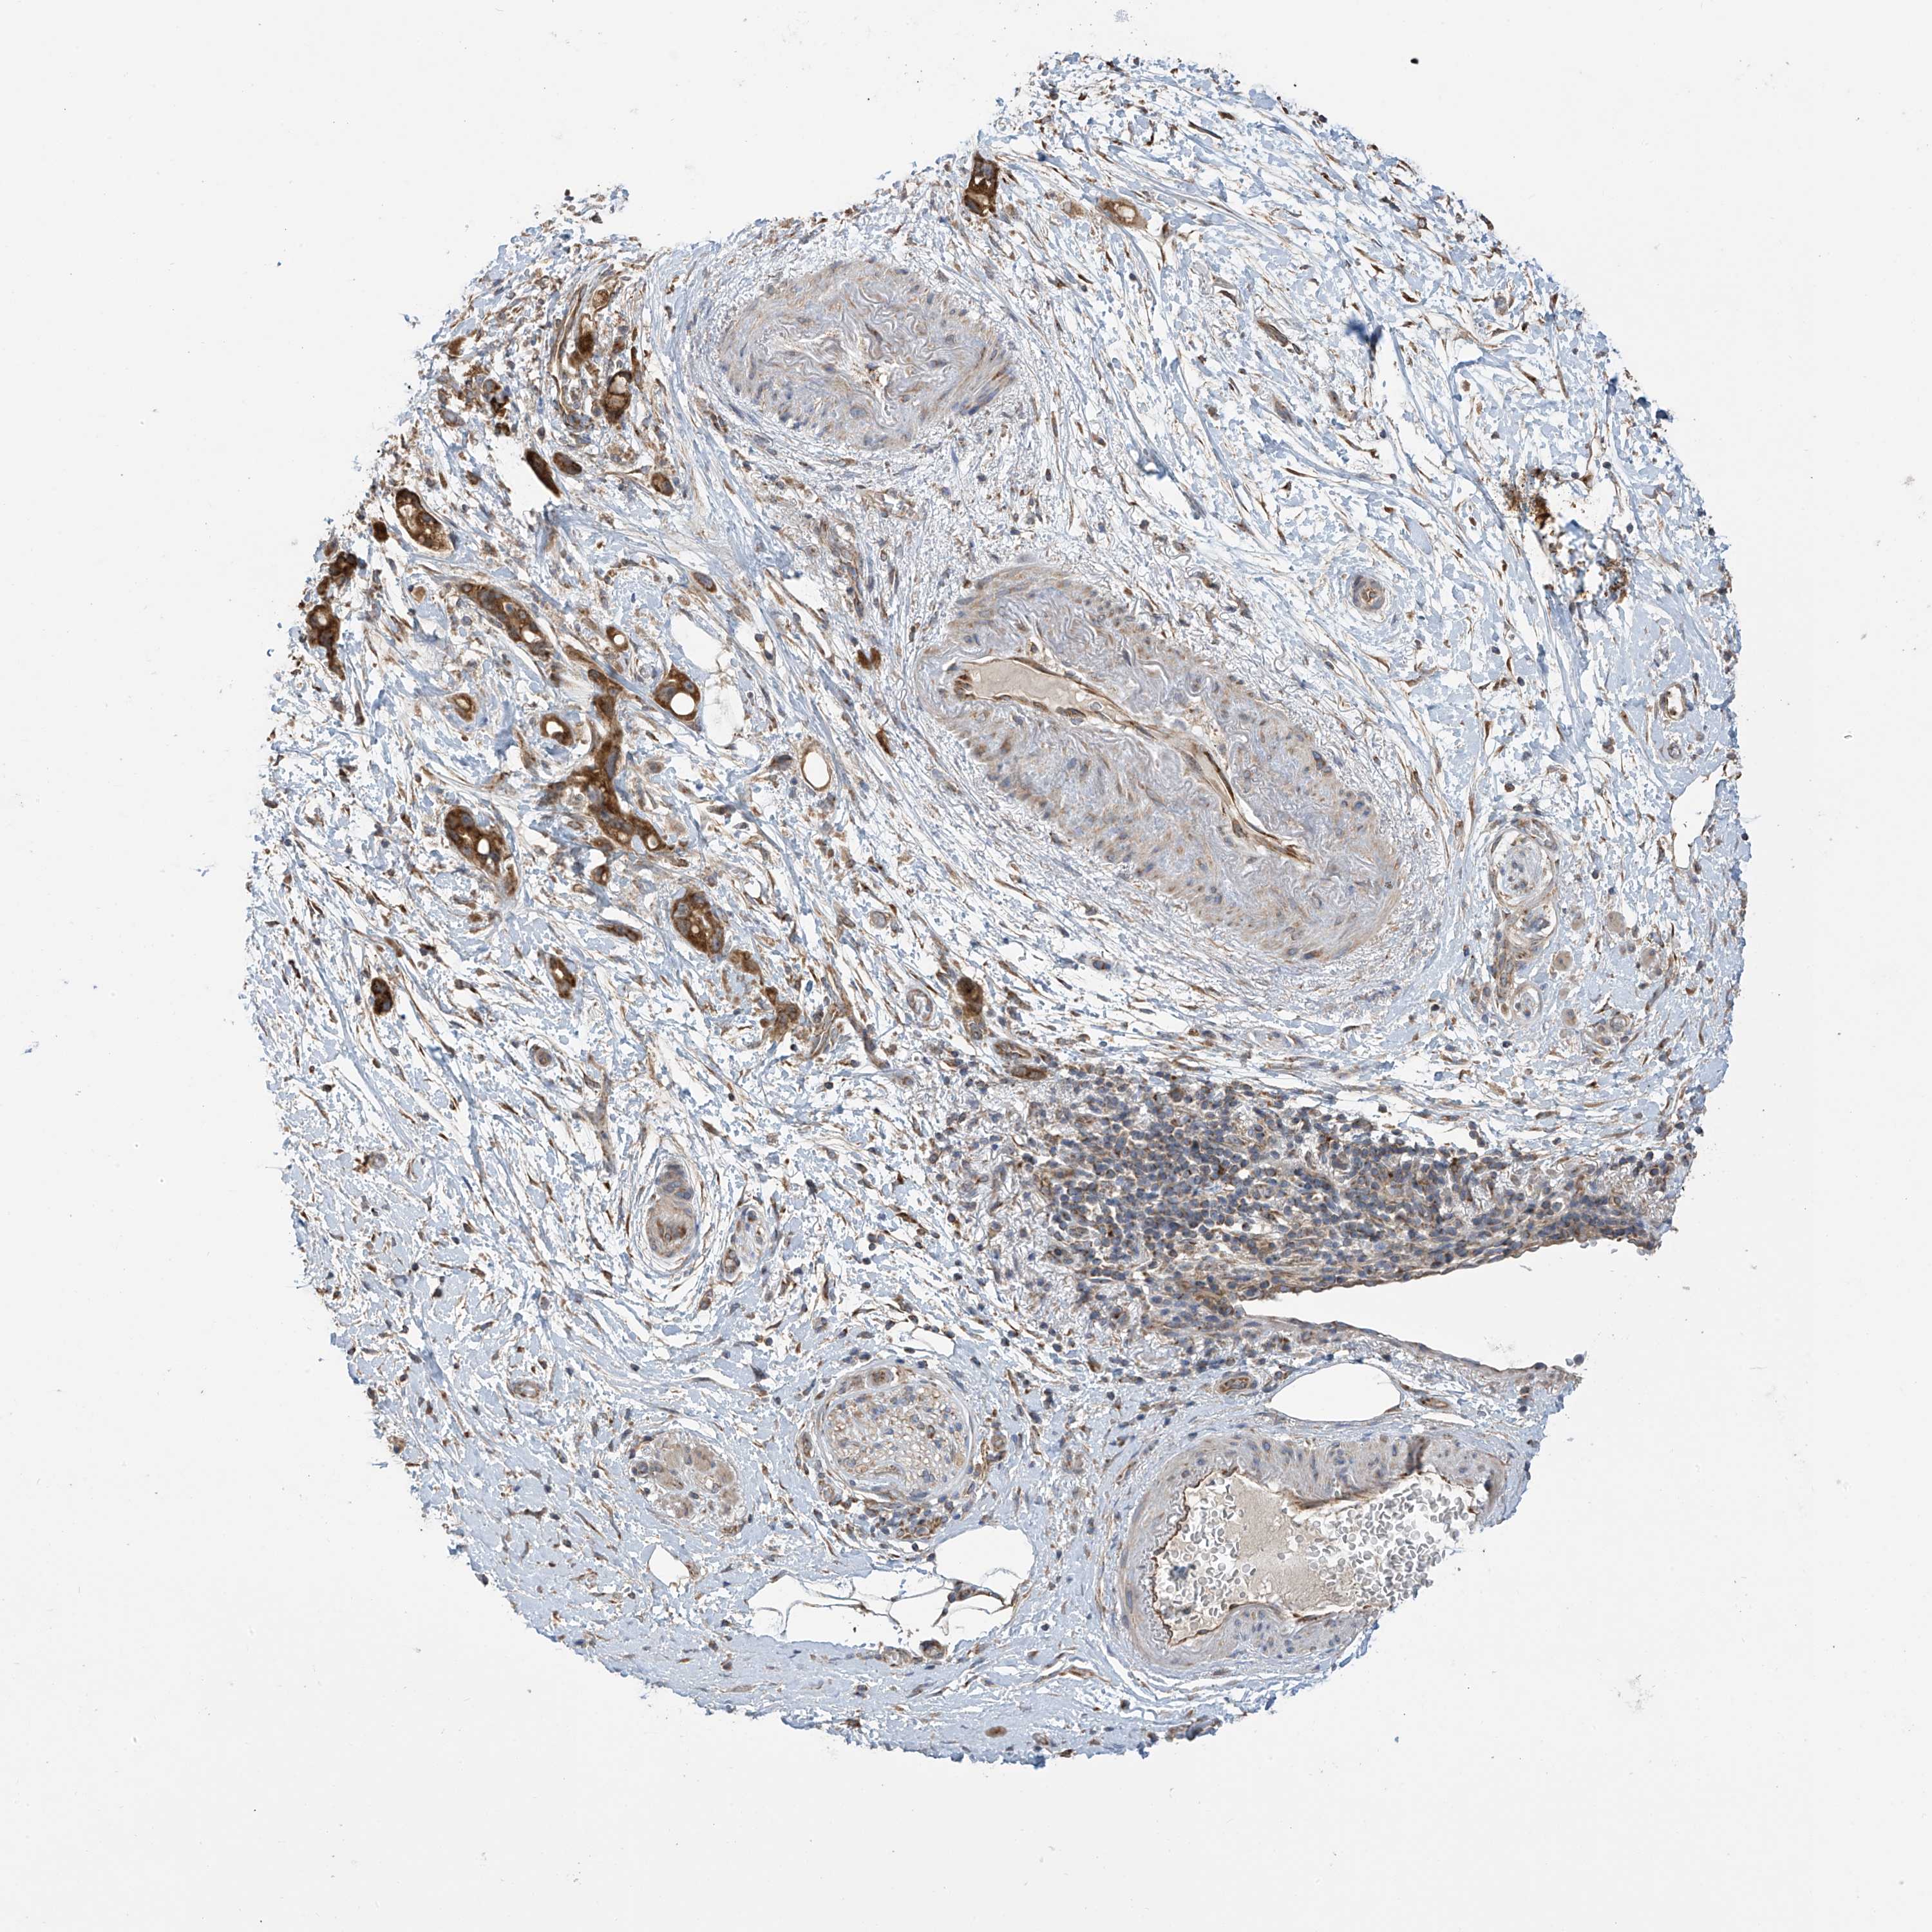

PANCREATIC CANCER - Protein expressioni

A mouse-over function shows sample information and annotation data. Click on an image to view it in a full screen mode. Samples can be filtered based on level of antibody staining by selecting one or several of the following categories: high, medium, low and not detected. The assay and annotation is described here.

Note that samples used for immunohistochemistry by the Human Protein Atlas do not correspond to samples in the TCGA dataset.

Antibody stainingi

Antibody staining in the annotated cell types in the current human tissue is reported as not detected, low, medium, or high, based on conventional immunohistochemistry profiling in selected tissues. This score is based on the combination of the staining intensity and fraction of stained cells.

Each image is clickable and will lead to virtual microscopy that enables deeper exploration of all samples and also displays staining intensity scores, fraction scores and subcellular localization as well as patient and tissue information for each sample.

Antibody HPA034602

Antibody HPA034603

Antibody CAB033424

Staining

High

Medium

Low

Not detected

Intensity

Strong

Moderate

Weak

Negative

Quantity

>75%

75%-25%

<25%

None

Location

Nuclear

Cytoplasmic/membranous

Cytoplasmic/membranous,nuclear

Adenocarcinoma, NOS